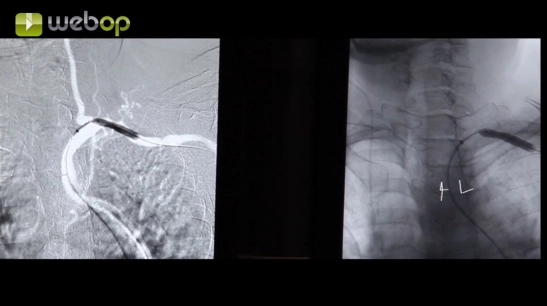

Aorta y lecho vascular pélvico

Angioplastia transluminal percutánea con implantación de stent en estenosis de arterias renales bilaterales.